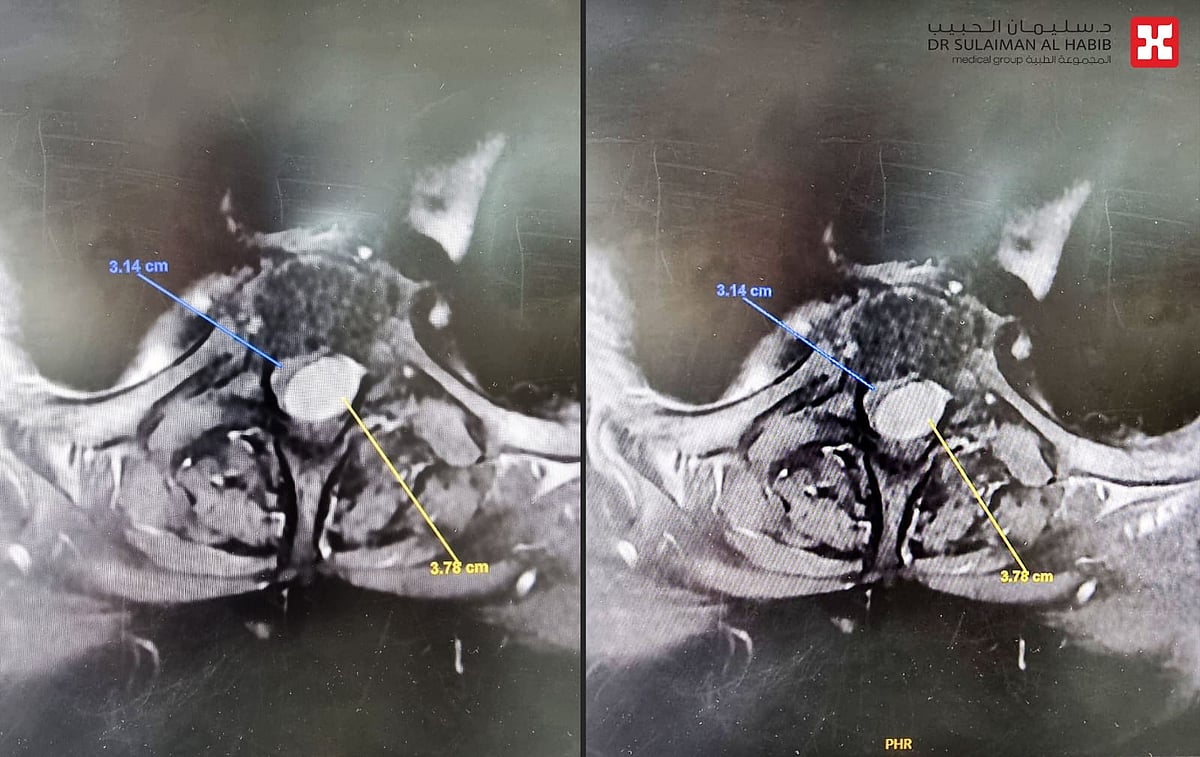

بفضل من الله- أعاد مركز طب وجراحة المخ والأعصاب، لمجمع الدكتور سليمان الحبيب الطبي بالعليا، القدرة على الحركة لـ”ستينية”، أقعدها ورم ضاغط على النخاع الشوكي خلف الفقرتين الثانية والثالثة الصدرية، إضافة إلى أنها عانت أيضاً من تضيق متوسط الحدة بالقناة الشوكية، وأجرى لها فريق طبي بقيادة د.عبدالله النبهان استشاري جراحة المخ والأعصاب والعمود الفقري جراحة مجهرية دقيقة وناجحة.